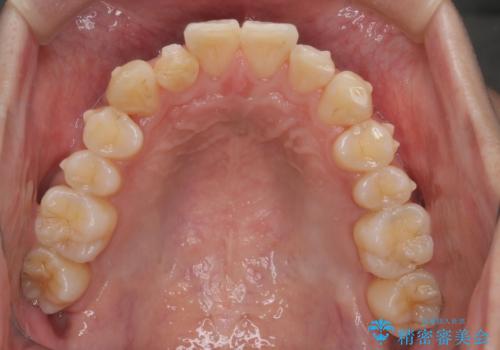

前歯のガタガタを治したい。

- 凸凹を治したいと来院された患者様です。

インビザラインにて、遠心移動を行いながら綺麗に配列することができました。